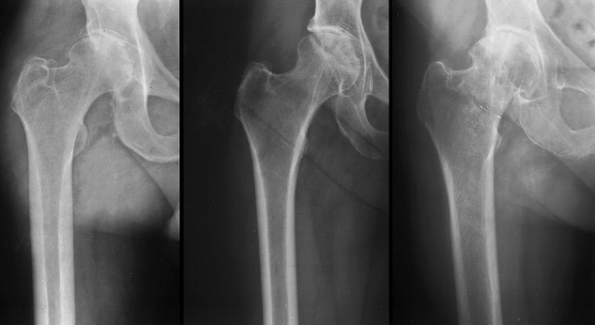

porous-coated femoral implants for patients with Dorr type A bone (Fig. 105.2), uncemented proximally coated metaphyseal filling implants for young patients with Dorr type B bone (Fig. 105-3), and cemented femoral

![]() |

Figure 105.2. AP radiograph of an uncemented total hip arthroplasty using an extensively porous-coated femoral component.

Figure 105.3. AP radiograph of an uncemented total hip arthroplasty using a proximally hydroxyapatite-coated uncemented stem.

Figure 105.4. AP radiograph of a hybrid total hip arthroplasty using an uncemented socket and a cemented stem.

Figure 105.5. The Dorr classification of femoral bone morphology (36).

The proximal femoral morphology is helpful in determining the favored femoral implant geometry and type of fixation. From left to right: Type A, Type B and Type C bone. |